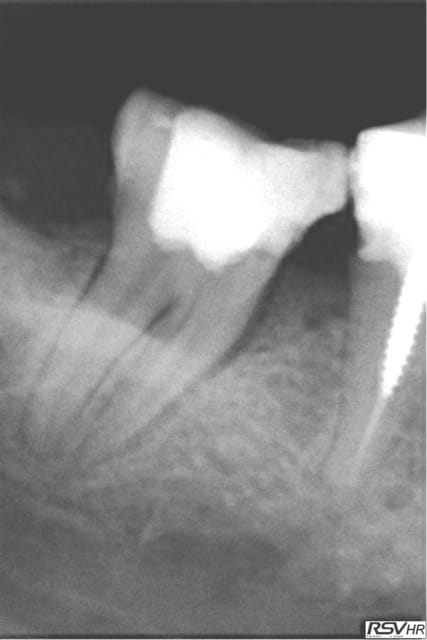

Tiens les endos de la semaine, que d'apex défoncés !-))

La 47 en fin le distal est obturé au système B (bouchon apical) et au mac spaden pour la partie coronaire, tu vois la différence à la radio ? Alors l'apex défoncé il faut avoir l'oeil ! peut etre mais à 25 centièmes et à conicité 6 %........-))

Tu as fait des progrès. Disons par exemple que sur la deuxième prémolaire, tu es allé un poil trop loin, ce qui a réduit sérieusement la constriction apicale. Peut être que que tu mesures ta LT un demi millimètre plus longue que nécessaire.